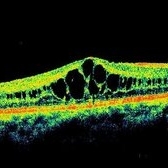

Inherited Cystoid Macular Edema

Inherited Cystoid Macular Edema

May 4 2014 by Mallika Goyal, MD

Right eye OCT of a 30-year-old male patient with bilateral inherited cystoid macular edema. There is no history of diabetes, hypertension, ocular surgery and there is no family history of similar eye problem. There is no fluorescein leakage at the macula as might be anticipated in an eye with cystoid macular edema.

Photographer: Mallika Goyal, MD, Apollo Health City, Jubilee Hills, Hyderabad, India

Condition/keywords: cystoid macular edema (CME), optical coherence tomography (OCT)